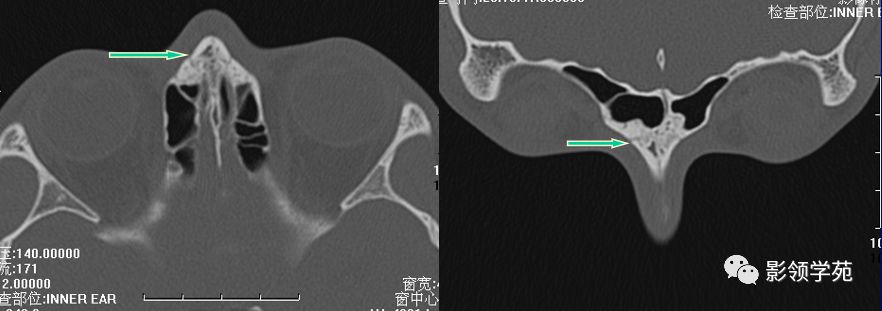

右侧鼻骨骨折

左上颌骨额突骨折

双侧鼻骨骨折

双侧上颌骨额突骨折